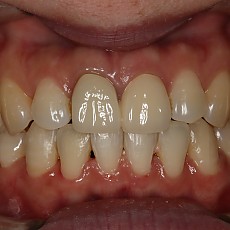

시술전후사진 12 페이지

Total 189건 12 페이지